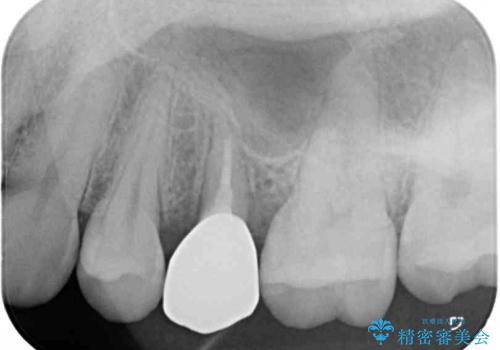

その後骨形成処置を行い、治癒を待って補綴治療を行うこととしました。

かなり深い位置にまで虫歯が及んでいたため、かなりの量を引っ張り出す必要があり、残された歯根は短く小さい状態となりました。

今後も定期的にレントゲンを撮るなど、経過を追っていく必要があります。